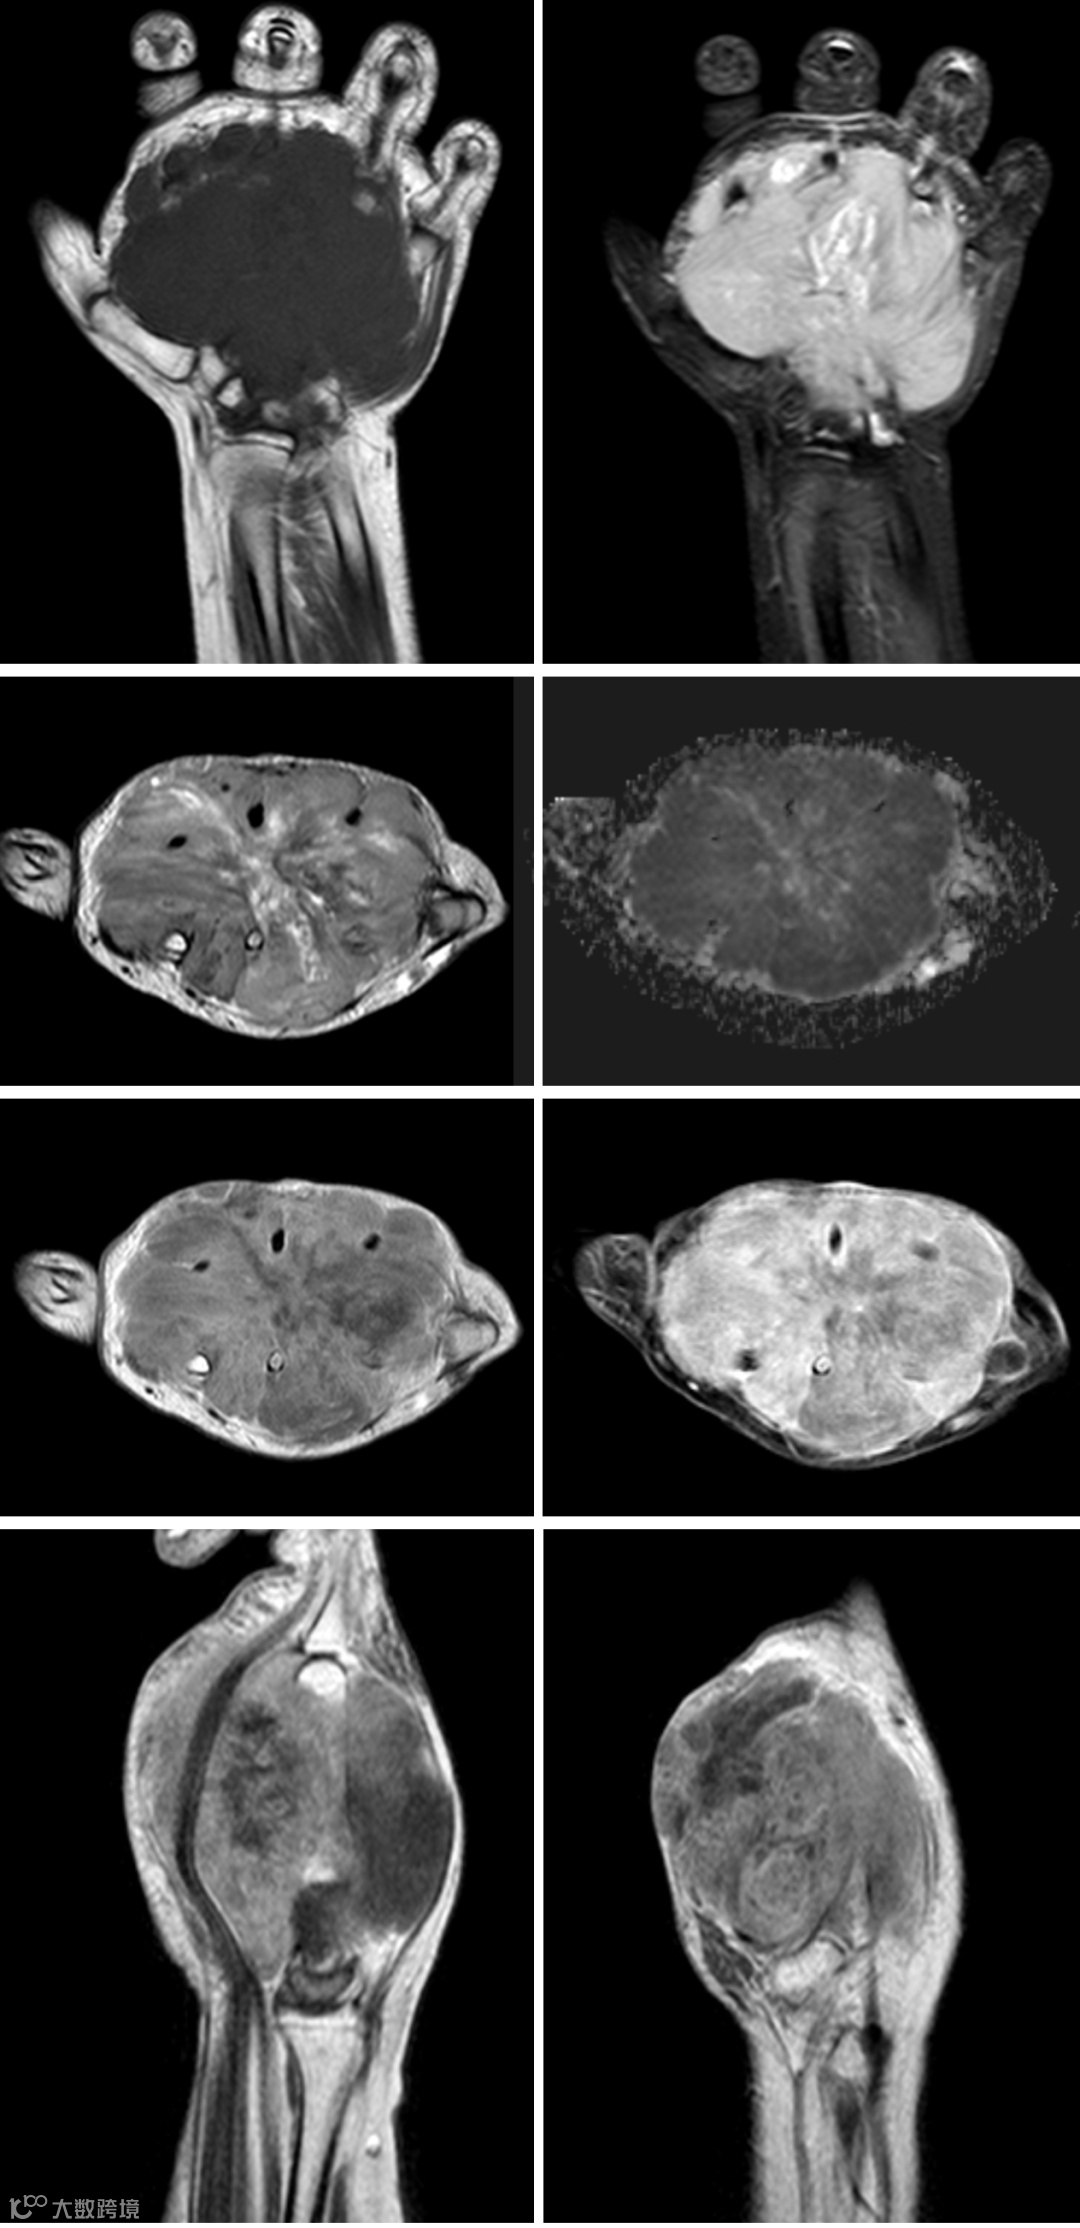

MRI

T1WI:等或低信号

T2WI:高信号

DWI: RMS恶性程度高,细胞排列紧密,DWI序列呈高信号

出血和钙化在RMS中较少见

增强扫描:因肿瘤内部液化坏死而强化不均匀,典型表现为“葡萄征”,即边缘强化明显,内部富含黏液基质则不强化

动态对比增强扫描:RMS的时间-信号强度曲线呈速升平台型,T2WI高信号的坏死区和黏液成分无强化

患者,女,12岁,近几月手部进行性增大,病理活检结果为胚胎性横纹肌肉瘤。手部MRI图像(部分图像)可见一个大的软组织肿块,其体积为7.8X6.7X8.6cm,沿着手掌掌侧和背部占据手掌,掌侧肿块更大。病灶在T1 WI呈中等信号,在T2WI和 STIR上呈高信号,增强扫描后呈明显的不均匀强化。肿块填充了掌指骨间隙并侵入相关肌肉,包裹了手的屈肌腱和拇屈肌腱。肿块也向背部破裂,围绕伸肌腱。可见肿瘤肿块侵入第二至第五掌骨,在第四掌骨最明显,近端部分完全侵蚀。还可见远端腕骨受侵犯。